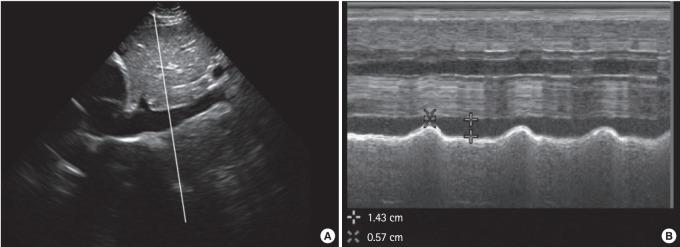

Resuscitation with intravenous fluid can restore intravascular volume and improve stroke volume. However, in unstable patients, approximately 50% of fluid boluses fail to improve cardiac output as intended. Increasing evidence suggests that excess fluid may worsen patient outcomes. Clinical examination and vital signs are unreliable predictors of the response to a fluid challenge. We review the importance of fluid management in the critically ill, methods of evaluating volume status, and tools to predict fluid responsiveness.

静脉输液复苏可恢复血管内容量并改善心输出量。然而,在不稳定患者中,约50%的液体冲击未能按预期改善心输出量。越来越多的证据表明,过多的液体可能会使患者的预后恶化。临床检查和生命体征并不是预测液体冲击反应的可靠指标。我们综述了危重症患者液体管理的重要性、评估容量状态的方法以及预测液体反应性的工具。